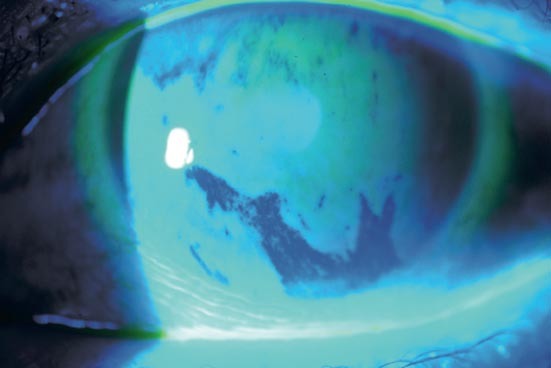

Patient consultant pour sécheresse oculaire. Quel test réalise-t-on ici?

Break up time: instillation d’une goutte de fluorescéine et mesure du temps de rupture du film lacrymal